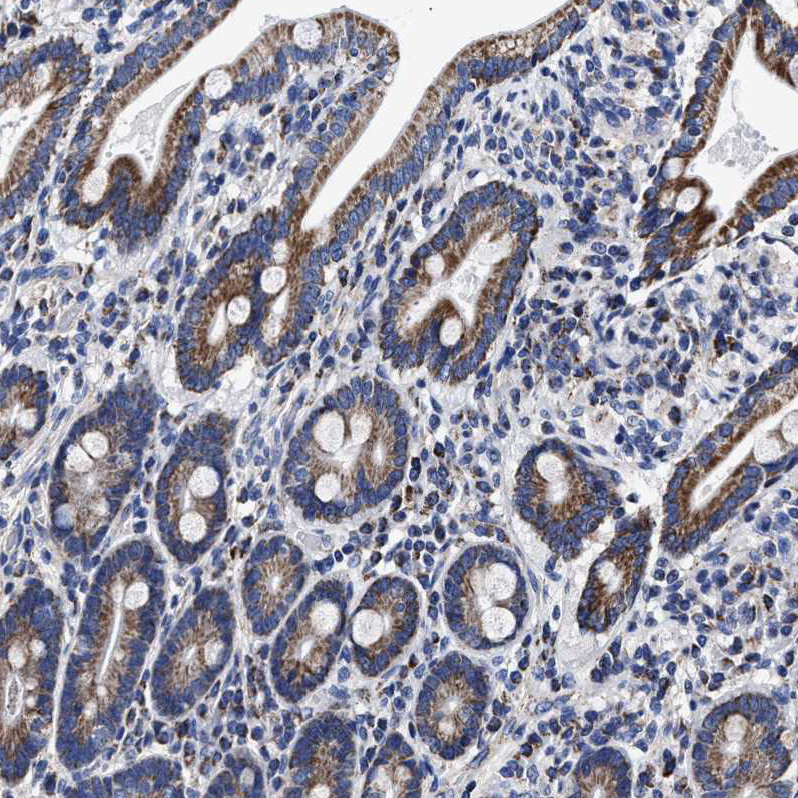

Immunohistochemical staining of human fallopian tube, gastrointestinal, kidney and testis using Anti-HINT2 antibody HPA020961 (A) shows similar protein distribution across tissues to independent antibody HPA059109 (B).